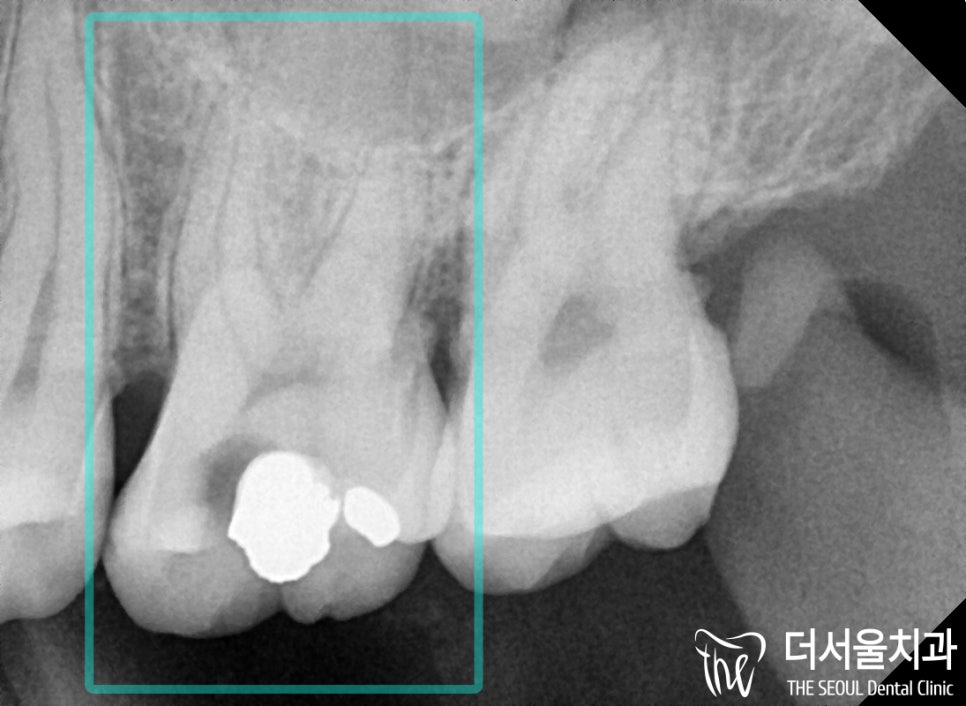

구강 내를 살펴보면

더욱 확연히 드러나는 것을 알 수 있습니다.

기존 보철 밑으로 심하게 썩어있는 충치와

치아 파절 의 범위를 확인할 수 있네요.

충격이 가해진 곳이 범위가 일부분이라도

이 환자처럼 보철이 씌워져 있는 경우에는

약해진 기존 보철에도 충격이 전달되어

이렇게 큰 손상이 나타날 수 있습니다.

아무래도 레진 및 인레이로는

수복이 불가능하겠다는 판단이 들었는데요.